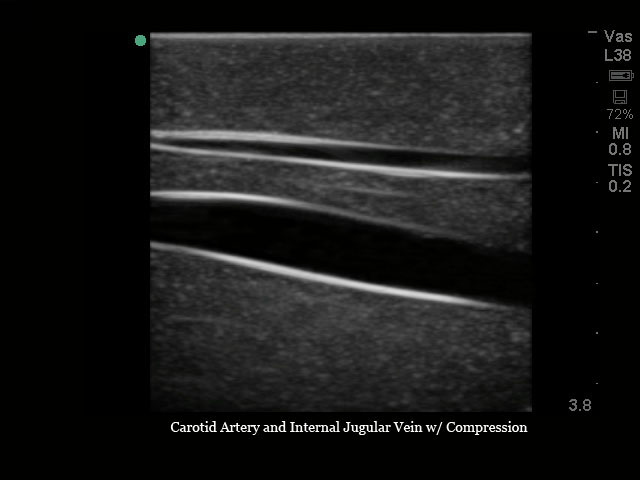

超声引导下颈内中心静脉穿刺术超声训练模块

型号:PC-BP009/PC-BP009.01

模型提供了极佳的真实感,给练习中心静脉置管术提供了最为经济实惠的操作模型